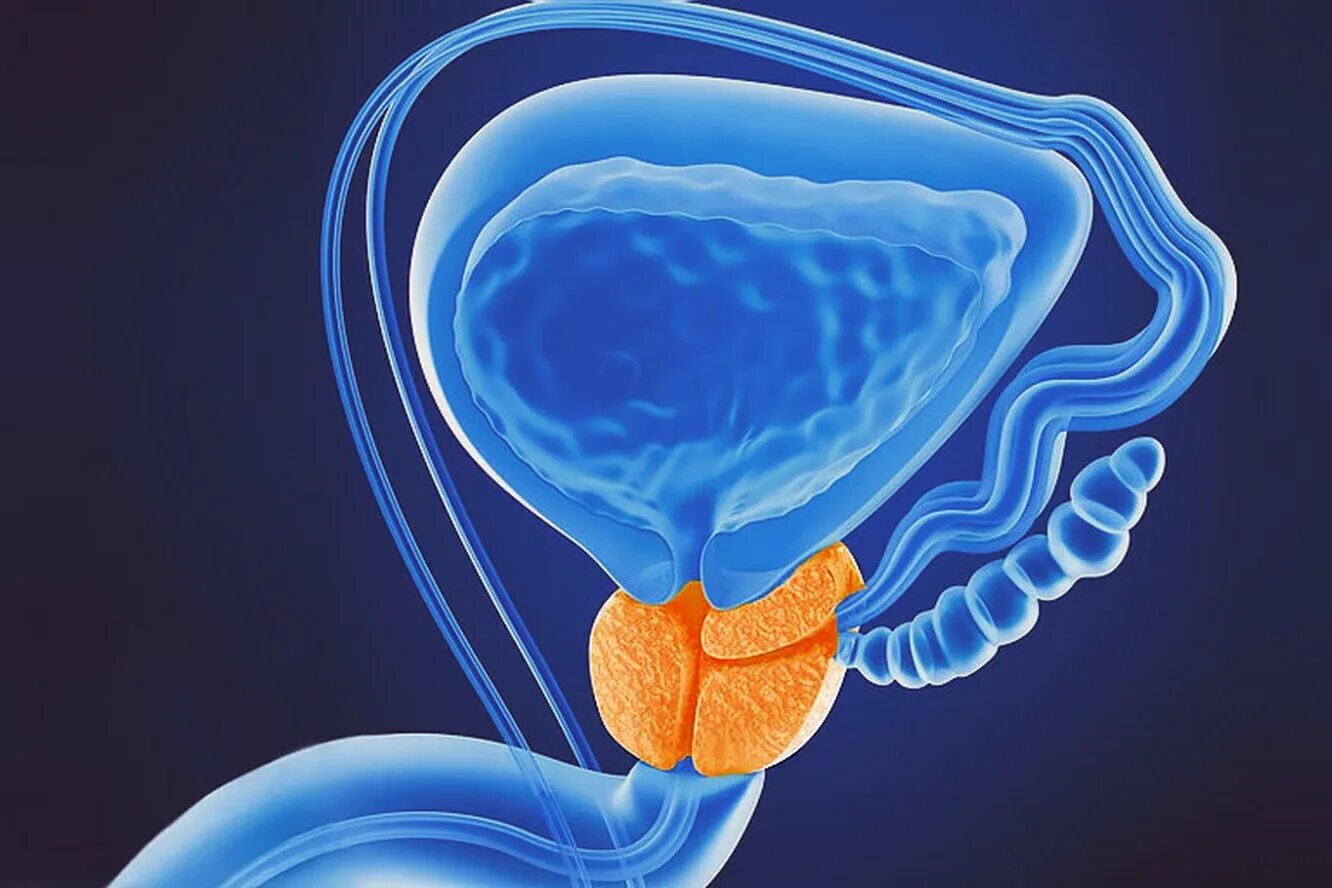

Злокачественное новообразование предстательной железы. Карцинома предстательной железы. Susp BL предстательной железы что это. Tumor предстательной железы Предстательная железа, Prostata. Карцинома предстательной железы. Простата и предстательная железа. Предстательная железа 3д

Предстательная железа, Prostata. Карцинома предстательной железы. Простата и предстательная железа. Предстательная железа 3д Ракпристательныйжелезылечение. Лекарство онкология предстательной железы. Лучевая терапия опухоли предстательной железы

Невринома предстательной железы. Опухоль предстательной железы. Опухоль простаты симптомы. Увеличение предстательной железы кт Предстательная железа фото

Предстательная железа фото Онкология предстательной железы. Степени опухолей простаты. Предстательная железа rak. Стадии опухоли простаты

Аденома простаты злокачественная. Онкология предстательной железы. Карцинома предстательной железы. Аденокарцинома простаты Увеличенная предстательная железа. Предстательная железа у мужчин

Увеличенная предстательная железа. Предстательная железа у мужчин

Сосудисто нервный пучок предстательной железы. Экстракапсулярная экстензия предстательной железы что это. Лучевая диагностика предстательной железы. Инвазия капсулы предстательной железы Предстательная железа у мужчин. Представительна яжелеза. Опухальпредседательнойжелезы

Предстательная железа у мужчин. Представительна яжелеза. Опухальпредседательнойжелезы Трансректальное УЗИ предстательной железы. УЗИ трузи предстательной железы. Карцинома предстательной железы УЗИ. Опухоль предстательной железы УЗИ